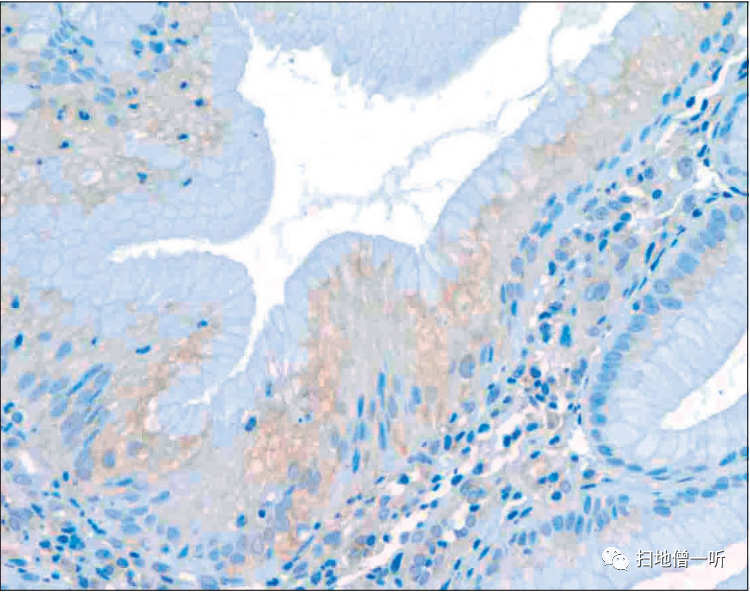

【多发白色扁平隆起】(春间·川口病)

患者70多岁,女性,白光观察发现散在性白色小扁平隆起。

▲在放大观察中,观察到了条纹状的微细粘膜图案。

▲在病理组织学上,表层的腺窝上皮出现了增生性变化。

另外,在长期服用PPI的人中,以胃体部为中心,有时会出现散在性的白色扁平小隆起。本病变被称为多发性白色扁平隆起(春间·川口病变),有报告称在PPI服用病例中出现频率较高。病理组织学上发现小凹上皮增生。